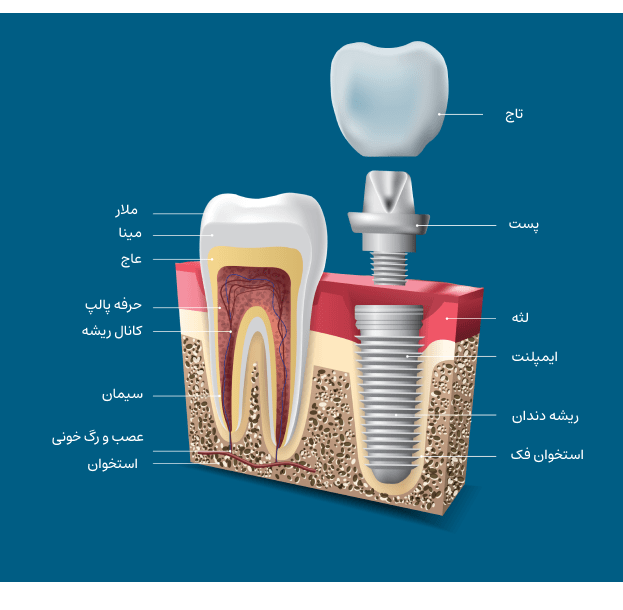

ایمپلنت دندان از بهترین روشهای درمانی برای جایگزینی دندانهای از دست رفته است. این روش به کمک پایههای فلزی از جنس تیتانیوم که در استخوان فک کاشته میشود، یک ریشه مصنوعی برای دندان جدید فراهم میکند. سپس تاج دندان ساخته شده از مواد مقاوم و طبیعی روی این پایه نصب میشود.

مدت زمان کامل درمان بسته به شرایط بیمار بین 3 تا 6 ماه است. در ابتدا پایه فلزی در استخوان فک قرار داده میشود و سپس زمان لازم برای جوش خوردن آن با استخوان فک طی میگردد. پس از گذشت این زمان تاج دندان روی پایه نصب میشود.

دندان ایمپلنت، روش پیشرفته و دائمی برای جایگزینی دندانهای از دست رفته است. در روش ایمپلنت دندان یک پایه فلزی در استخوان فک قرار میگیرد. این پایه نقش ریشه دندان طبیعی را ایفا میکند و پس از جوش خوردن با استخوان میتواند تاج مصنوعی دندان را روی خود حمل کند. دندان ایمپلنت عملکرد و ظاهری مشابه دندان طبیعی دارد.

ایمپلنت دندان فرایند چند مرحلهای است که شامل مشاوره و معاینه اولیه، جراحی کاشت ایمپلنت، دوره التیام و جوش خوردن، قرار دادن اباتمنت و نیز ساخت و نصب تاج دندان خواهد بود.